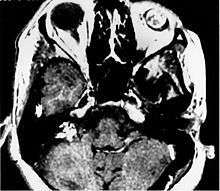

Imaging studies help to identify the tumor and the specific anatomic site of involvement. Magnetic resonance images show a hyperintensity (hypervascularity) of a heterogeneous mass by T1 weighted images. Computed tomography shows a multilocular, lytic destructive temporal bone mass, centered within the endolymphatic sac (between internal auditory canal and sigmoid sinus).[1][5][6]